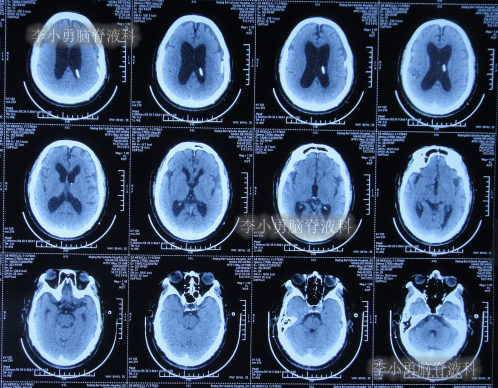

2021年4月16日(腰大池腹腔分流术后19天),因意识变差,查头部CT(图-4)后,急诊进行了硬膜下血肿引流术,并升高分流泵的压力200。

图-4:2021年4月16日头部CT